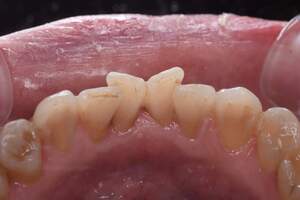

歯石除去

治療前

治療後

| 年齢 | 31歳・女性 |

|---|---|

| 主訴 | 主訴:歯石除去 部位:全顎 |

| 治療内容 | 初診検査・歯石除去 |

| 治療期間 | 2週間 |

| 費用 | 合計:約4,000~5,000円 内訳 初診料:約3,000~4,000円 (保険診療) 歯石除去:約1,000円 (2023年1月現在) |

| リスク・副作用 | ・歯肉の炎症がある場合は歯石除去中に出血を伴う可能性があります。 ・処置後に歯がしみることがあります。 ・歯茎の炎症が軽減すると歯茎が引き締まり、歯が長く見えることがあります。 |

| 治療方針 | 前歯部に叢生(歯列不正)があり多量の歯石が認められました。炎症の抑制を優先するため初診時はTBIのみ行い、2回目以降で歯石除去を行いました。今後は縁下歯石(歯ぐきの中に付着する歯石)の除去を全顎的に行っていく予定です。 |

| 担当者所見 | 叢生(そうせい)とは歯が折り重なるようにデコボコにはえている状態をいいます。歯ブラシが難しく磨き残しをしやすい為、普段使用している歯ブラシに加えワンタフトという細かい部分も磨くことのできる小さな毛束の歯ブラシの使用をおすすめしました。 |

| 担当者所見 | 歯石の存在は感じていたものの歯科医院に苦手意識が強く3年ほど放置していたとのことでした。 舌で触った時にザラザラすることや口臭も気になった為、今回意を決してご来院くださいました。 ブラッシング指導を熱心に聞いてくださり、セルフケアで歯肉の炎症を抑えた上で歯石除去ができたのでお痛みが少なく行えました。 患者様も苦手意識が克服できたと喜んでくださり、今後の治療にも積極的な姿勢です。 |